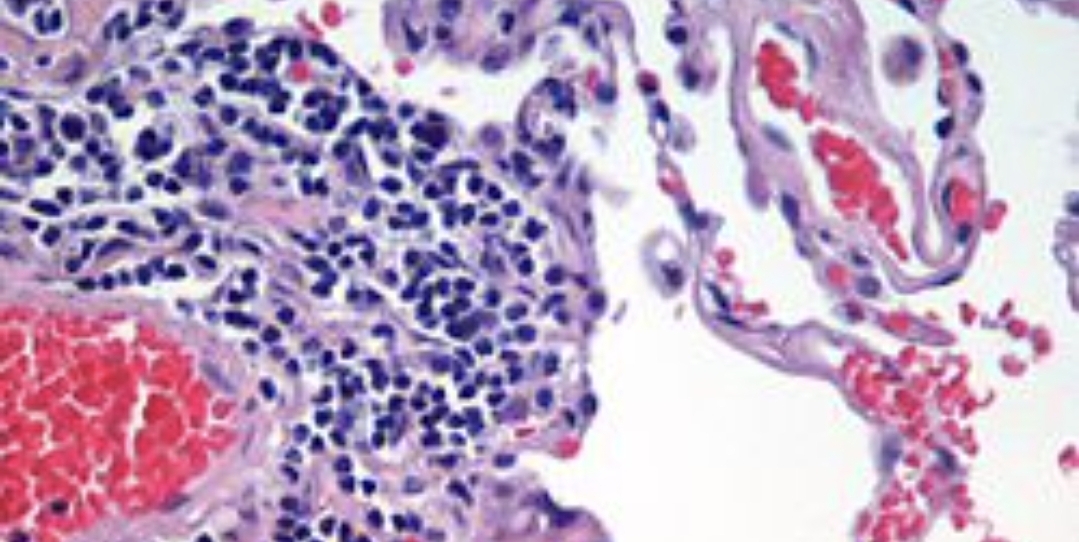

Godine 1908. ruski histolog Aleksandar Maksimov (1874.-1928.), je napisao “najcjenjeniji udžbenik na svijetu u histologiji”, knjigu koja je postala standardni tekst za studente medicine i doživjela je 12 izdanja. Također je razvio i uveo unitarnu teoriju hematopojeza, teoriju na kojoj se temelji moderni koncept podrijetla i diferencijacije krvnih stanica.